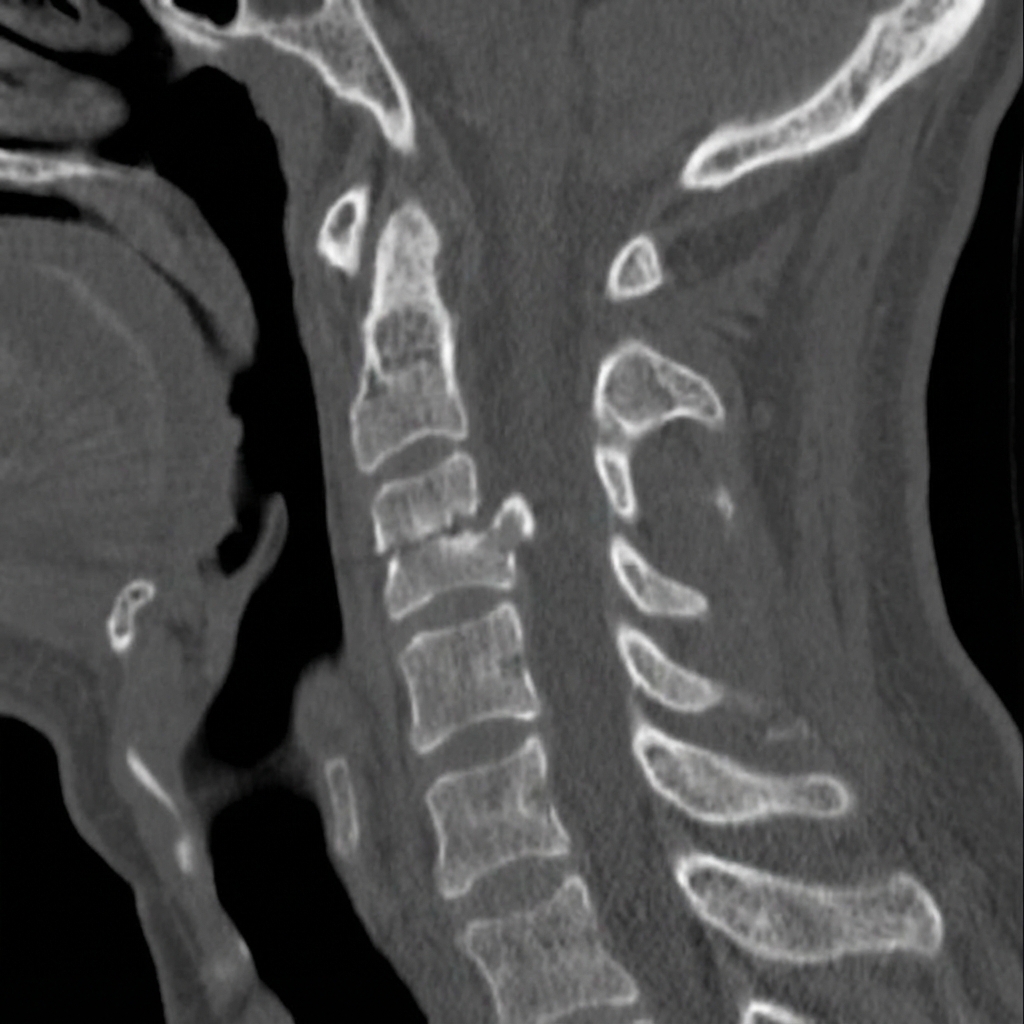

Sagittal and coronal CT images demonstrating Type II odontoid fracture at the base of the dens with 4mm posterior displacement of the dens relative to the C2 body. The fracture line is at the junction of the odontoid process and C2 body - the watershed zone for blood supply. This represents a Type II odontoid fracture in an elderly patient with high non-union risk requiring surgical stabilization.

Describe the CT findings and classify this fracture.